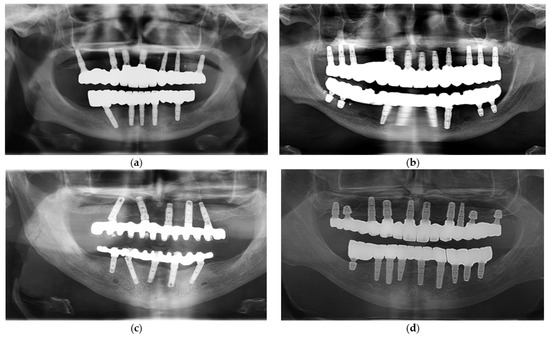

Preliminary Comparative Analysis of Monolithic Zirconia and Hybrid Metal–Ceramic Designs in Full-Arch Implant-Supported Restorations

by Sergiu-Manuel Antonie, Laura-Cristina Rusu, Ioan-Achim Borsanu and Emanuel-Adrian Bratu

Prosthesis 2025, 7(6), 154; https://doi.org/10.3390/prosthesis7060154 - 1 Dec 2025

Background: Material choice in full-arch implant-supported restorations significantly impacts longevity, complication rates, and patient satisfaction. This retrospective study compared monolithic zirconia versus hybrid metal–ceramic full-arch designs over a minimum three-year follow-up. Methods: Twenty patients (9 female, 11 male; mean age 55.4 ± 7.5 [...] Read more.

Background: Material choice in full-arch implant-supported restorations significantly impacts longevity, complication rates, and patient satisfaction. This retrospective study compared monolithic zirconia versus hybrid metal–ceramic full-arch designs over a minimum three-year follow-up. Methods: Twenty patients (9 female, 11 male; mean age 55.4 ± 7.5 years) treated with full-arch implant-supported restorations were reviewed. Ten received monolithic zirconia restorations; ten received hybrid metal–ceramic. Clinical outcomes, including mechanical complications, prosthetic maintenance needs, opposing dentition wear, and patient-reported satisfaction (esthetics, comfort, masticatory function via VAS), were recorded. Statistical analyses were performed using Chi-square, independent t-tests, or Mann–Whitney U tests, with a significance level set at p < 0.05. Results: All implants (100%) and prostheses (>95%) survived. Monolithic zirconia exhibited no veneering chipping, while two events were observed in hybrid restorations (difference not statistically significant), and one bulk fracture occurred (monolithic). Hybrids had no framework fractures. Screw loosening occurred in one zirconia case. Mean VAS scores exceeded 9.0 in both groups; zirconia scored slightly higher for esthetics (9.4 ± 0.5 vs. 8.8 ± 0.6) and comfort (9.2 ± 0.6 vs. 9.0 ± 0.7). Polished zirconia resulted in no clinically detectable enamel wear, whereas hybrids with glaze loss caused occasional mild enamel wear but without functional impairment. Conclusions: Both restoration types show excellent survival and patient satisfaction over three years. Monolithic zirconia reduces veneering-related complications and maintenance, suggesting a possible advantage in functionally demanding cases with high occlusal loads or limited prosthetic space; hybrids may remain preferable when esthetic customization and gingival contour reproduction are paramount. Full article